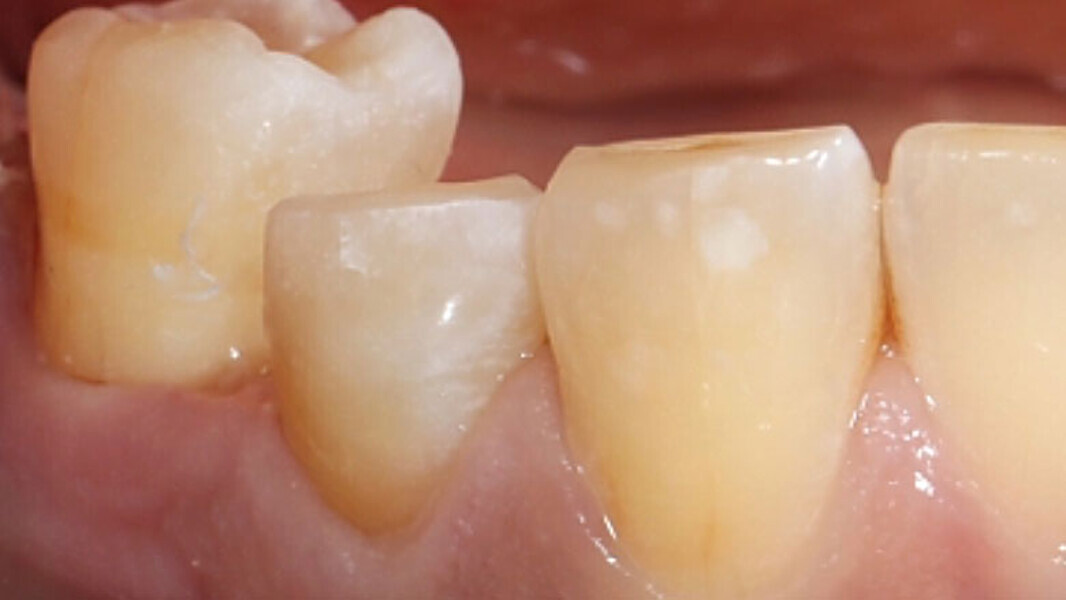

Fig. 11. La restauración de cerámica de feldespato durante la prueba clínica en boca.

Fig. 12. Desde vestibular no se observaban transiciones entre la restauración y el diente.